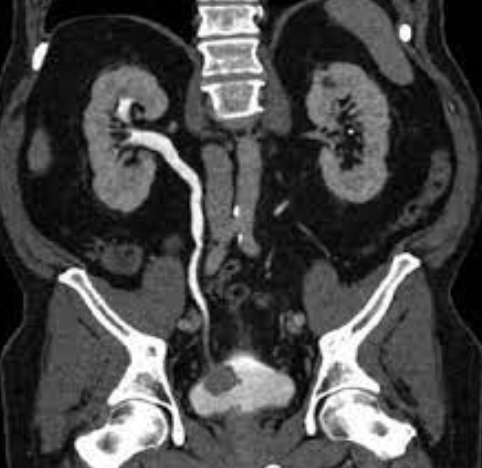

TAC

Hidronefrosis

Quistes renales